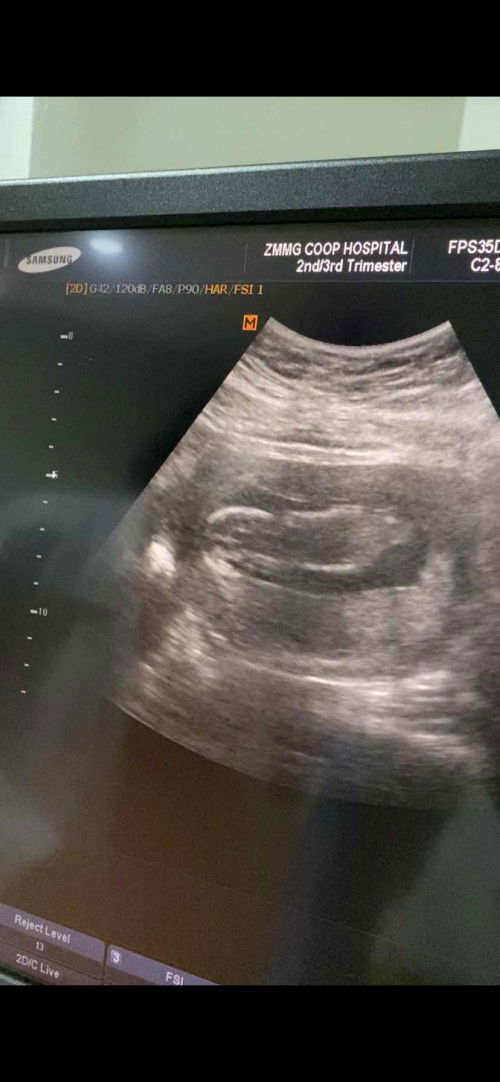

My baby's gender

Hi mommies! Sharing with all of you my 12weeks and 3days scan. This is my second pregnancy nadin. Super laki ko this time, daig ko pa 6 months. Ask ko lng sana if may possibility ma malaman ang gender at 17 weeks? Hehe. Excited lang kami at maraming team girl. 😅☺️ TIA 💕